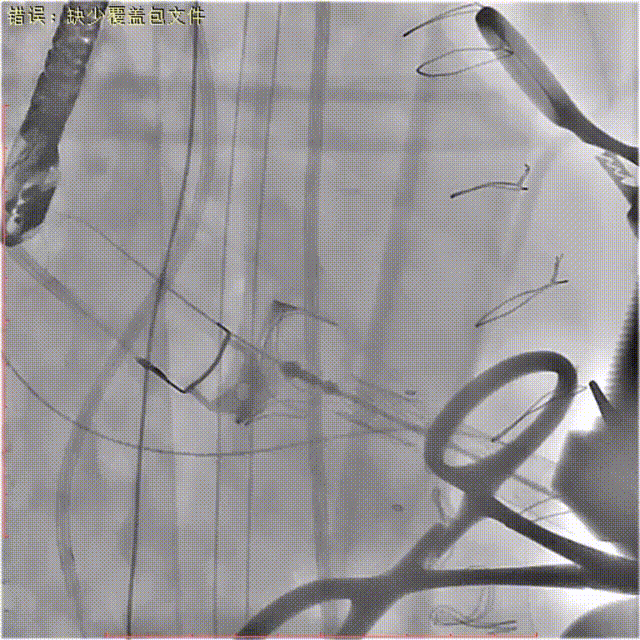

释放定位件,确保定位件位于生物瓣瓣窦内,推送植入瓣膜至瓣环平面,打开瓣膜支架,支架释放后退出导管输送系统。

瓣膜定位

瓣膜释放

瓣膜扩张形态不满意,遂行球囊后扩。

球囊后扩

在食道超声定位引导下植入封堵器1枚。

超声引导定位下植入封堵器